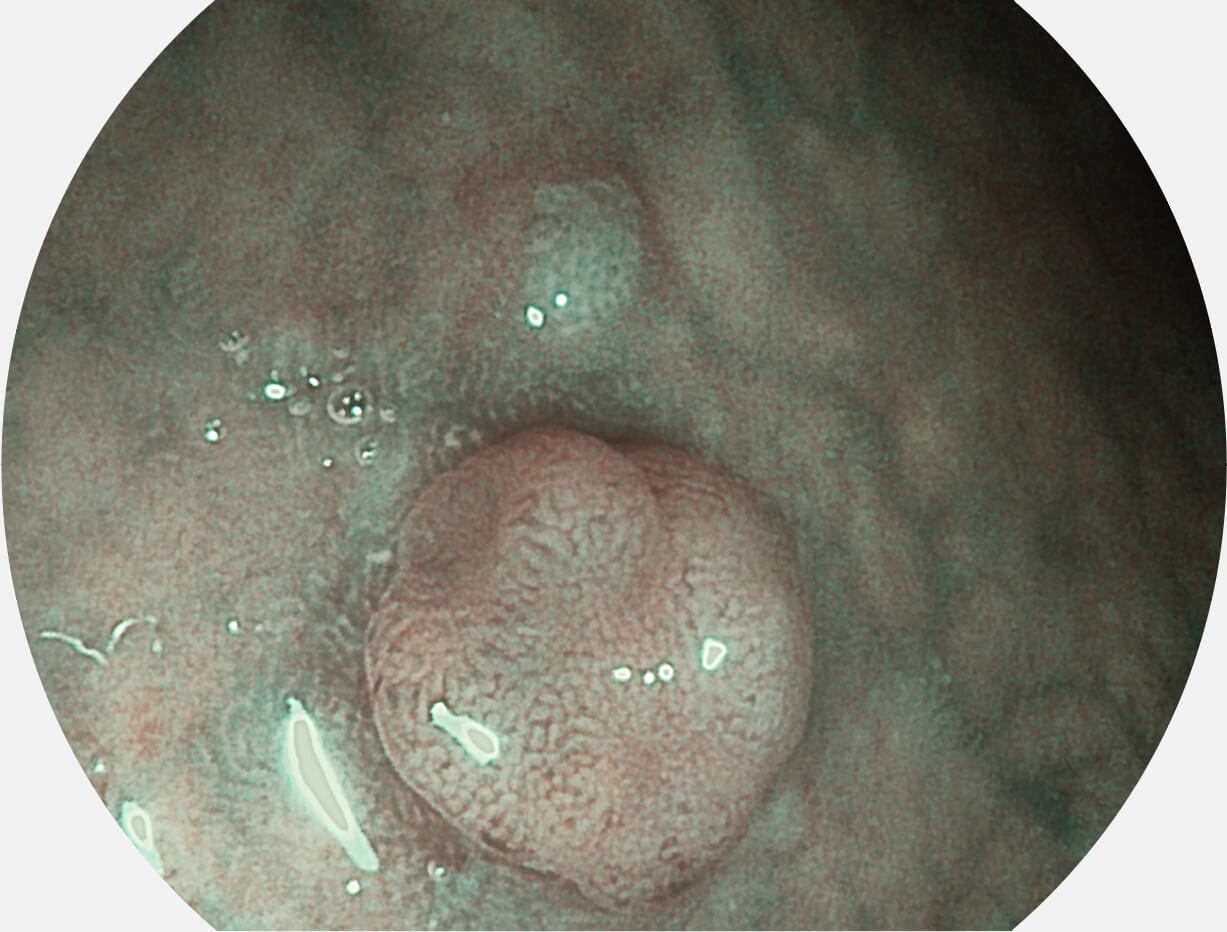

图像具有高亮度、高黏膜血管颜色对比度的特点,且不改变粘液、食物残渣、粪便的基本颜色,可在中远景下进行观察,助力消化道早期疾病的诊断。

SFI图像

强调浅层黏膜结构的同时,保证照明亮度和提升浅层微血管与中层血管颜色对比度,病变边界更清晰。

VIST图像

采用光路合束技术,光谱自由度高,实现了更丰富的照明模式,染色模式SFI及VIST,从远景到近景,助力消化道早期疾病诊断。